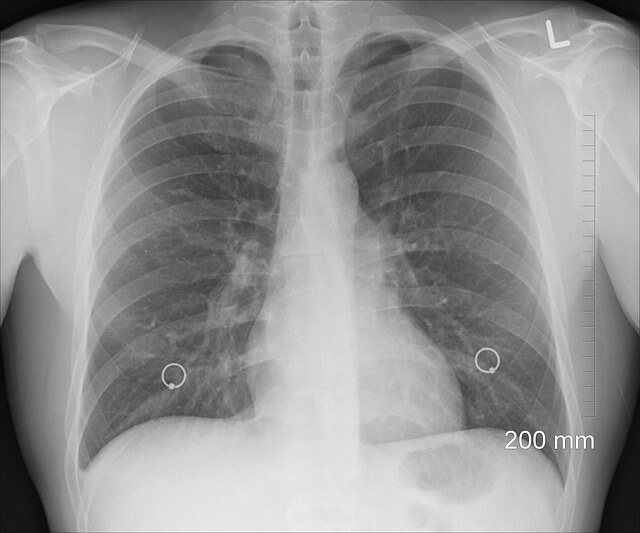

폐렴구균 예방접종 무료 대상자와 신청 방법 3. 백신 종류와 접종 기준 차이